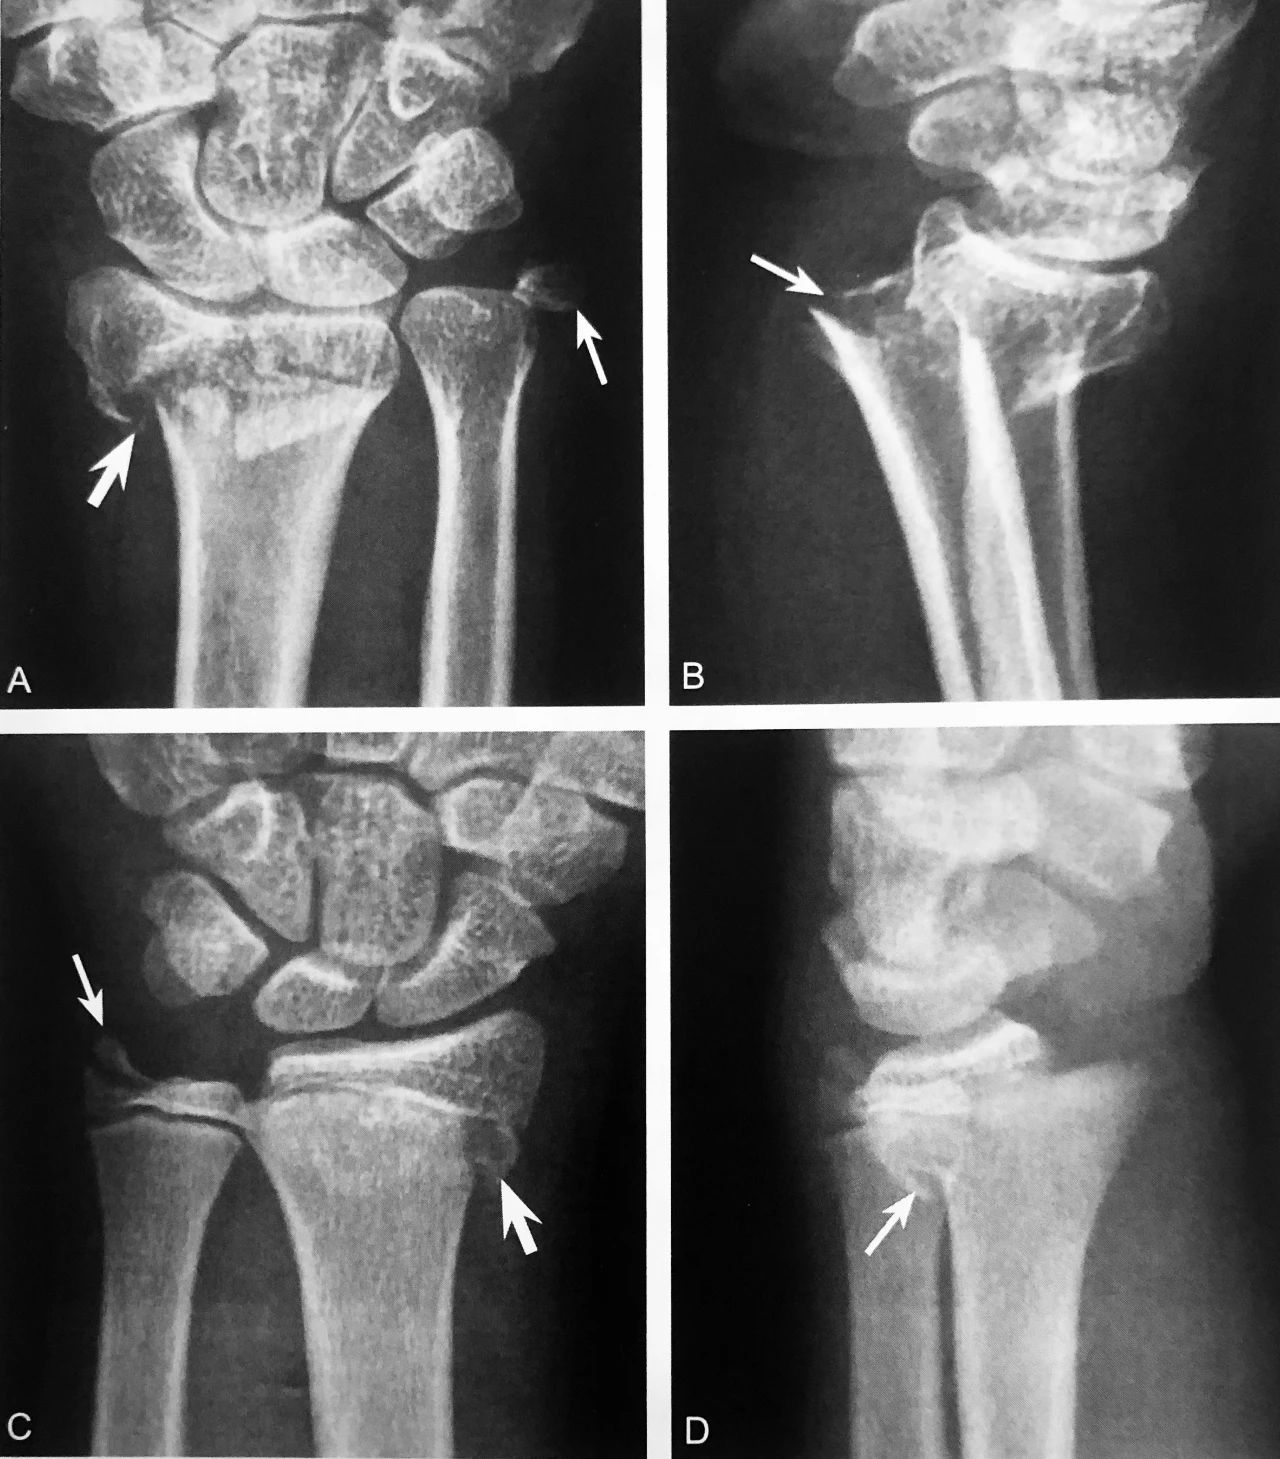

A~B.左腕关节ⅹ线正位及侧位。左桡骨远端骨折(粗箭头),尺骨茎突撕脱性骨折(细箭头),桡骨远端骨折背侧骨质嵌顿向掌侧成角(细箭头);C~D.右腕关节 ⅹ 线正位及侧位。桡骨远侧干骺端骨折伴骨骺向外侧移位(粗箭头),尺骨茎突部分撕脱(细箭头),桡骨远端骨骺向背侧移位,干骺端背缘碎骨片与骨骺相连(细箭头)

判读要点:

1、见于 Colles 骨折,桡骨远端骨折断端向掌侧成角,远端骨折块向背桡侧移位并旋后;

2、桡骨缩短,骨折处背侧骨质嵌入或粉碎骨折

3、腕背部软组织肿胀,活动受限,腕呈叉样畸形;

4、常合并尺骨茎突骨折,桡腕关节背侧半脱位等复杂损伤,导致腕关节不稳定。